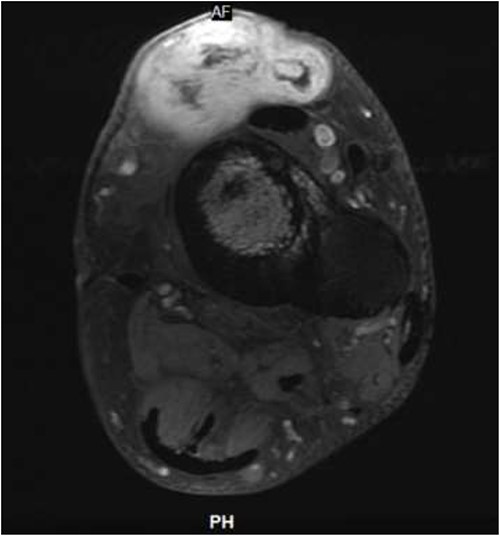

He presented upon noticing a lump overlying the rectus flap. On exam, the left lower extremity had multiple incisions with well-healed scars and a protruding lesion at the distal aspect of his previous incision, which was non-tender to palpation (Fig. 1). MRI of the lower extremity revealed a soft tissue mass in the anterior compartment of the left lower extremity (Figs 2 and 3). Biopsy of the lesion demonstrated RMS and molecular diagnostics revealed missense mutations in MYOD1 (p.L122R) and DOT1L (p.G1441R). Tumor cells were microsatellite stable. The copy number profile is suggestive of broad copy number gain of chromosome 5p. The patient was discussed at the local tumor board and was treated with D9803 chemo protocol (vincristine-based), receiving 4 cycles before proceeding to operative management.